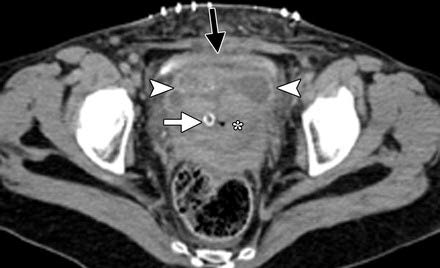

Figure 13: Axial contrast-enhanced CT image reveals a fluid collection (arrowheads) anterior to the lower uterine segment (*) and posterior to the bladder (black arrow), corresponding to a small bladder flap hematoma post caesarean section. The intrauterine balloon catheter can be seen (white arrow) [5].